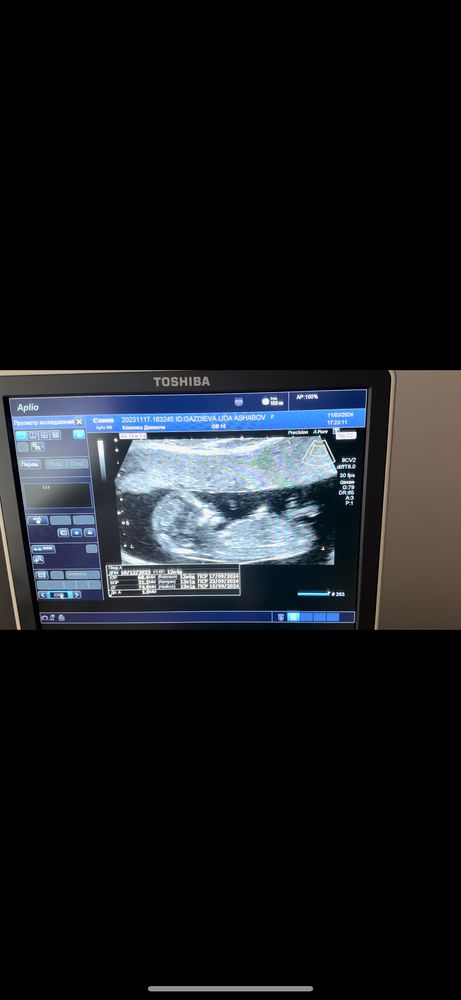

Пол ребенка Актиферт гино